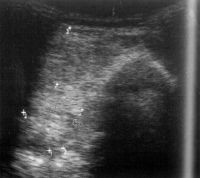

Az ultrahang néhány évtizede igen népszerűvé vált az orvosi gyakorlatban. Napjainkban talán a leggyakrabban alkalmazott képalkotó vizsgálat. A hanghullámokat piezoelektromos kristályok hozzák létre, mely hullámok a vizsgálat alkalmával részben elnyelődnek, részben pedig visszaverődnek. A visszavert hanghullám intenzitása alakítja ki a képpont "szürkeségét". A módszer előnye, hogy semmilyen kellemetlenséget, vagy kockázatot nem jelent a beteg, a vizsgált személy számára. Nem jár sugárterheléssel sem, ezért szükség esetén többször is ismételhető. Alapvizsgálat, melyet az orvosok a képalkotó módszerek közül általában elsőként alkalmaznak.

A korszerű vizsgálófejek (transzducerek) tartalmazzák a hanghullámokat generáló és érzékelő kristályokat is. Másodpercenként 24 kép, felvétel készíthető, tehát tulajdonképpen valósidejű mozgást tud érzékelni a vizsgáló. A transzducer-fejekben nagy technikai fejlődés volt ez elmúlt évtizedekben, így ma már speciális helyekre speciális "fejekkel" lehet behatolni (pl. a nyelőcsőbe, vaginába, végbélbe, egyes erekbe stb.) A jobb képminőség érdekében – külső felületen végzett vizsgálat esetén - a test és a vizsgálófej közé zselés anyagot juttatnak. A transzducer fej számítógéphez kötött, így a vizsgáló rögtön látja az eltéréseket, "real time"-ban tudja vizsgálni a szervek működését, a különböző áramlási jelenségeket.

Alkalmazása igen kiterjedt, a belszervek vizsgálatában. Ahogy a röntgen nem igazán alkalmas, a belszervek, "lágyrészek" vizsgálatára, az ultrahang viszont kiválóan, és kellő rugalmassággal. A hasi-, és a kismedencei szervek vizsgálatára rendkívül jól alkalmazható, tehát a vese, máj, lép, hasnyálmirigy, nagyerek, epe, a nyirokrendszer elemei jól vizsgálhatóak ultrahanggal. Pont a rugalmasság, a sokirányú látószög és a valósidejű leképezés miatt pontos képet alkot pl. daganatokról, cisztákról, az epe- és vesekövességről, esetleges elzáródásokról.